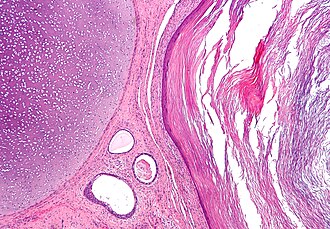

Zametni listići su osnovni slojevi stanica koji se stvaraju tijekom embriogeneze.[1] Svi pravi mnogostaničari (životinje koje su kompleksnije od spužve) stvaraju dva ili tri zametna listića. Životinje sa zrakastom simetrijom, poput žarnjaka, imaju dva zametna listića (ektoderm i endoderm) te su zato diploblastične. Životinje s bilateralnom simetrijom stvaraju i treći, srednji sloj (mezoderm), između ektoderma i endoderma. Zato su one triploblastične životinje. Zametni listići izazivaju nastanak svih životinjskih tkiva i organa tijekom procesa organogeneze.

Među svim životinjama, spužve su na najnižem stupnju organizacije, jer imaju samo jedan zametni sloj. Iako imaju diferencirane stanice (npr. hoanociti), nedostaje im prava tkivna organizacija. Diploblasticžne životinje, žarnjaci i rebraši, pokazuju veći stupanj složenosti, imajući dva zametna listića, endoderm i ektoderm. Diploblastične životinje su organizirane u prepoznatljiva tkiva. Sve više životinje (od plošnjaka do čovjeka) su triploblastične. One posjeduju i mezoderm između ona dva sloja koja imaju i diploblastične životinje. Triploblastične životinje razvijaju prepoznatljive organe.

Oplodnja vodi do stvaranja zigote. Tijekom sljedećeg razdoblja, procesa brazdanja, mitotičkim staničnim diobama zigota se transformira u šuplju kuglastu nakupinu stanica, blastulu. Ovaj rani oblik zametka prolazi kroz gastrulaciju, u kojoj se stvara gastrula s dva ili tri zametna listića. Kod svih kralježnjaka, ove stanice prethodnice diferenciraju u zrela tkiva i organe.[2]

Kod čovjeka, nakon otprilike tri dana, zigota mitotičkim diobama stvara morulu, čvrstu nakupinu stanica. Potom se pretvara u blastocistu, koja se sastoji od vanjskog sloja stanica zvanog trofoblast i unutranje stanične mase (embrioblast). Napunjena materničnom tekućinom, blastocista probija zonu pellucidu i podvrgava se implantaciji. Unutarnja stanična masa u početku ima dva sloja: hipoblast i epiblast. Na kraju drugog tjedna javlja se primitivna pruga. Epiblast u ovom području miče se prema primitivnoj pruzi, uvlači se u njezin donji dio i stvara novi sloj, endoderm, gurajući hipoblast prema van (hipoblast sudjeluje u stvaranju amniona.) Epiblast se nastavlja kretati i stvara novi sloj, mezoderm. Vršni sloj sada nosi naziv ektoderm.[3]